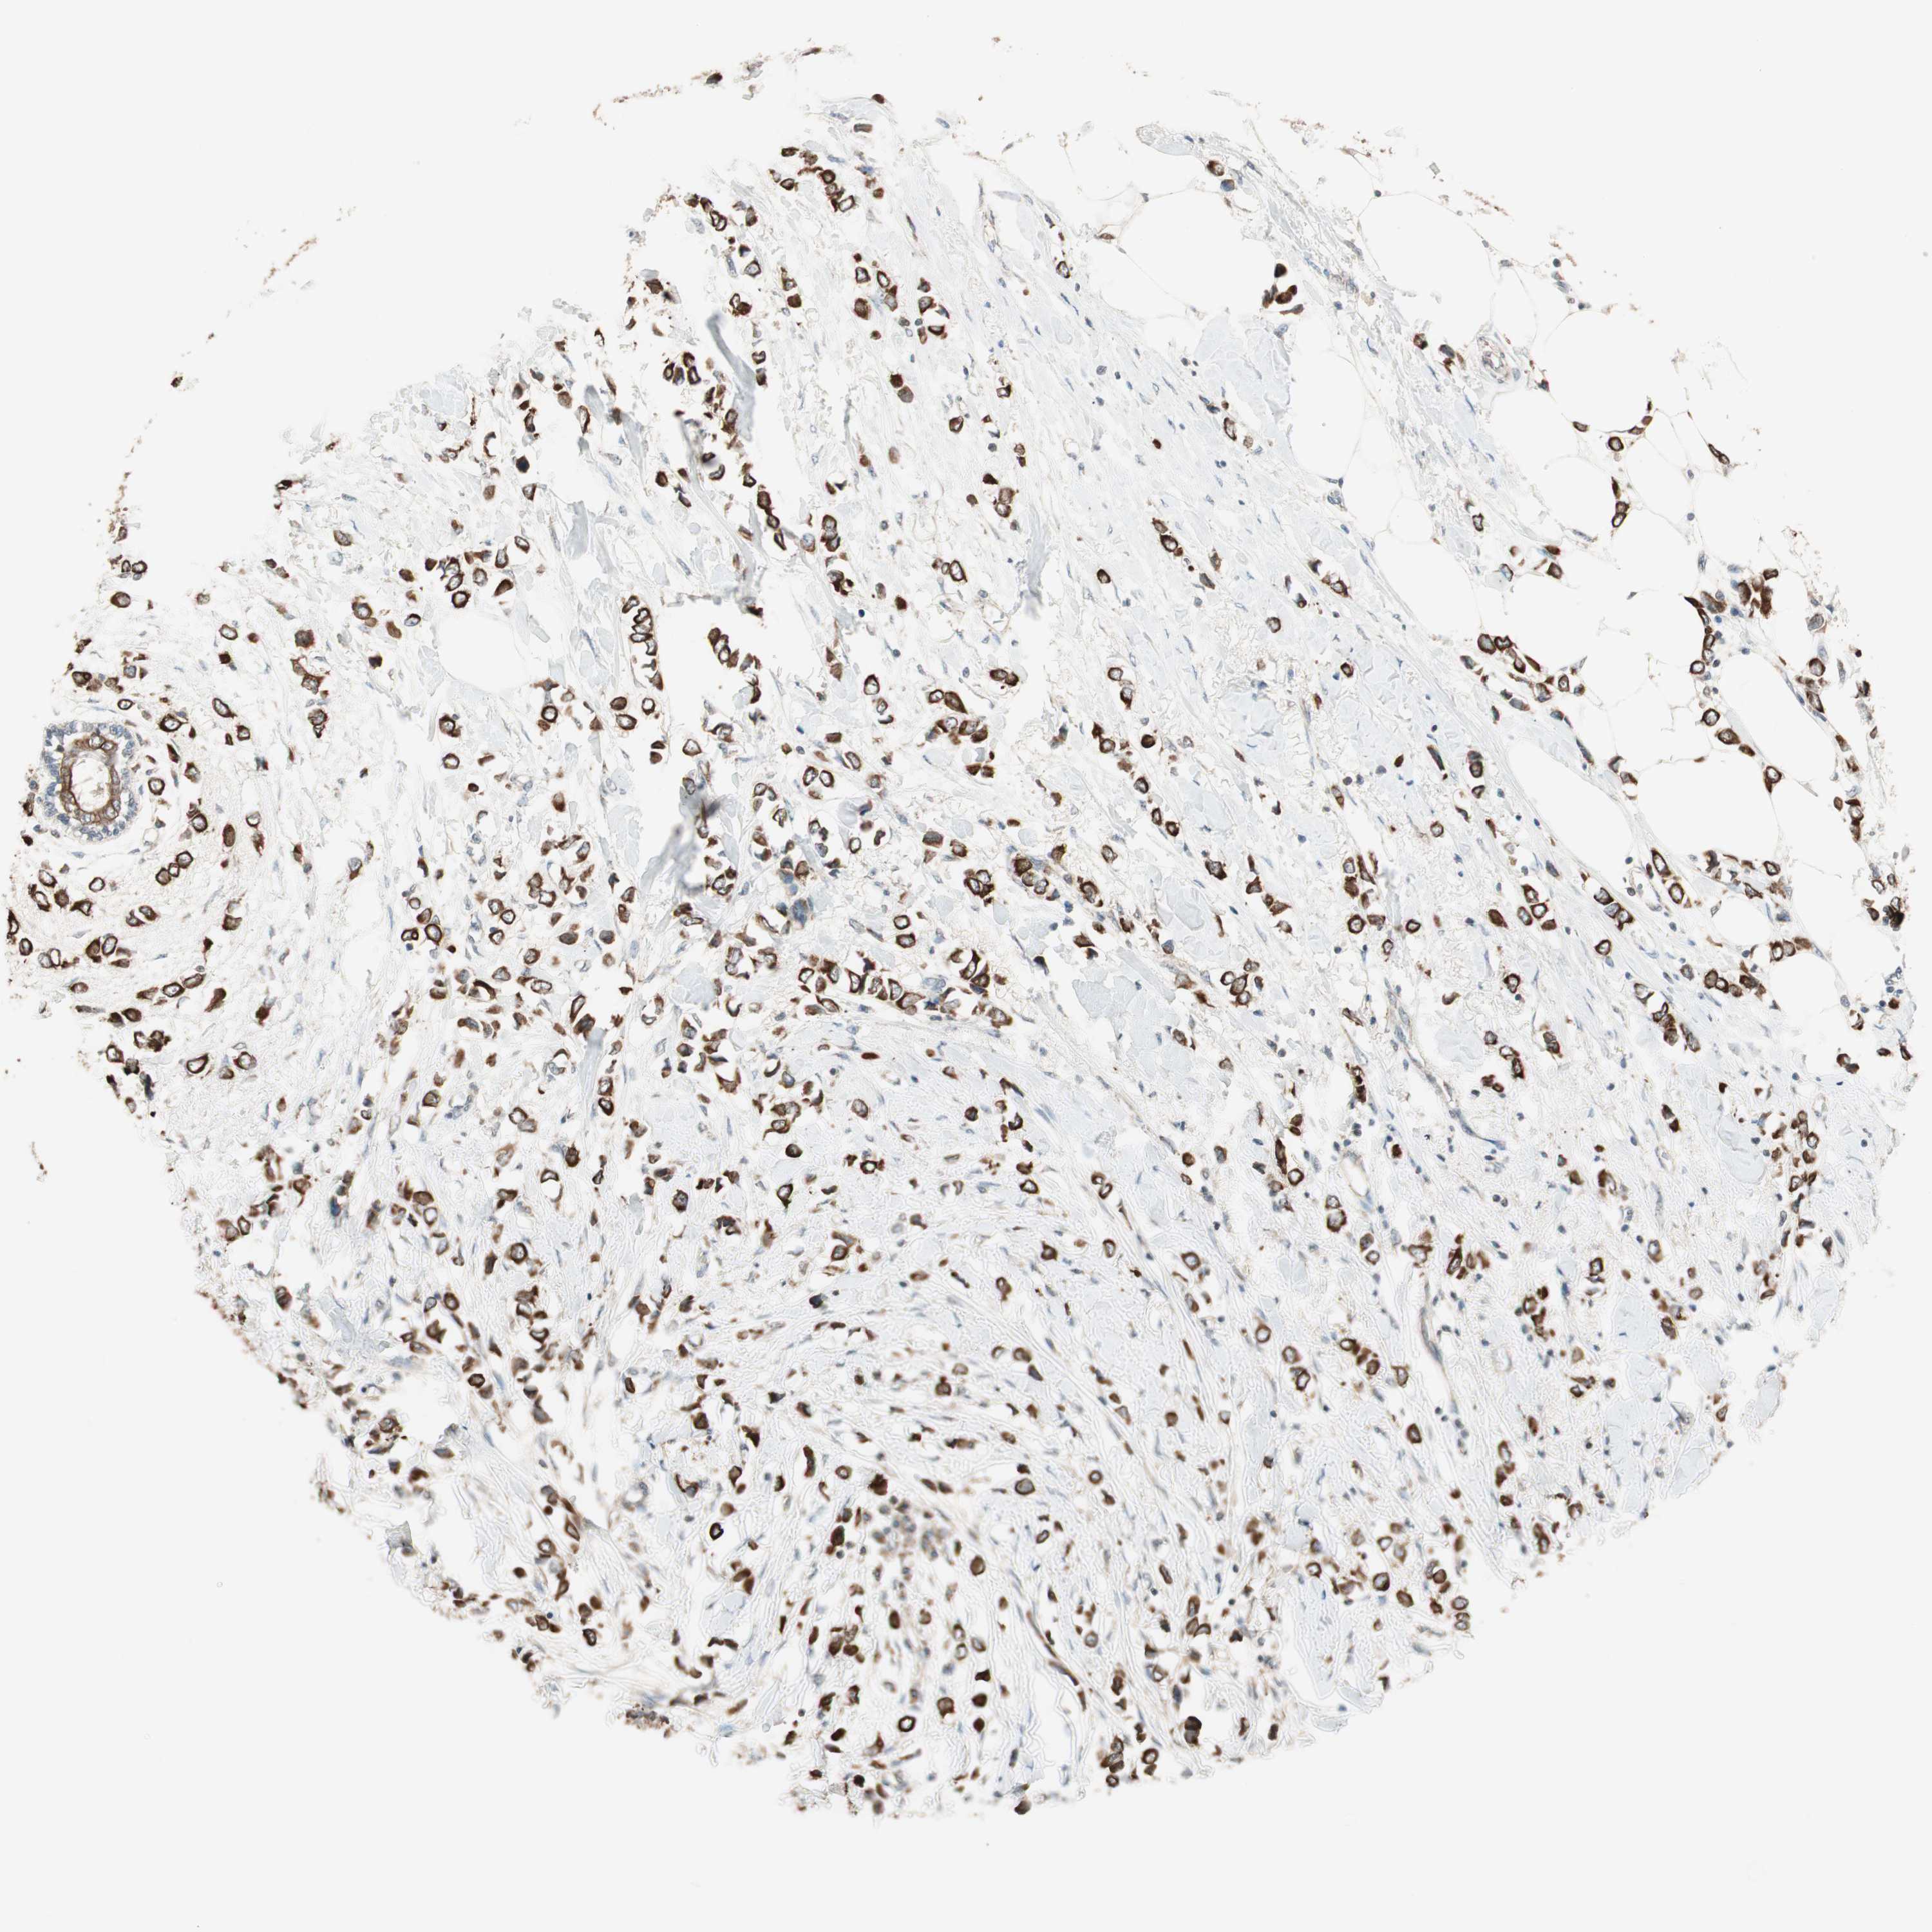

BRCA TCGA BRCA VALIDATION PROTEIN EXPRESSION

ANTIBODIES

AND

VALIDATION